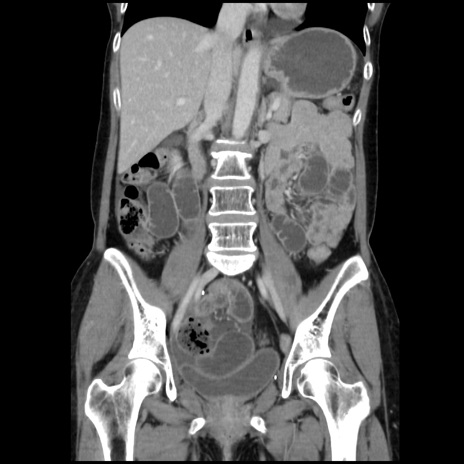

症例32(冠状断像)

【症例】40歳代 女性

【主訴】上腹部痛、嘔気・嘔吐

【現病歴】約9時間前頃から急に上腹部痛、嘔気、嘔吐が出現。改善しないため救急要請。

【既往歴】子宮頚癌(広汎子宮全摘術、放射線療法)、腸閉塞

【身体所見】腹部:平坦、軟、腸雑音亢進、上腹部を中心に腹部全体に圧痛あり。

【データ】WBC 8400、CRP 0.03